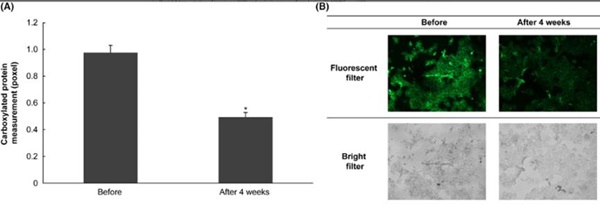

同时,外泌体还具有极好的抗氧化功能,携带的抗氧化成分能够清除自由基,减少氧化应激对黑色素细胞的影响,从而保护细胞免受损伤。

使用外泌体四周后皮肤产生抗氧化效果